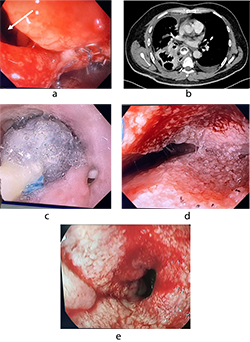

Endoscopic examination revealed a rounded lesion externally compressing an 8 cm segment in the lower third of the esophagus along the right lateral wall, with intact mucosa. Erosions measuring 3-5 mm with semicircular distribution were observed at the gastroesophageal junction, accompanied by reactive hyperplasia of the gastric mucosa (Fig. 3).

Contrast-enhanced CT of the chest, abdomen, and pelvis showed circumferential thickening and distortion of the abdominal esophagus and gastric cardia, with a mass measuring 48×78 mm and a density of 60-63 Hounsfield units (Fig. 4). perigastric lymph nodes were not radiologically visible. Isolated para-aortic lymph nodes up to 13 mm were noted.

Due to lesion size and extent, surgical enucleation was technically unfeasible. Minimally invasive Ivor Lewis esophagectomy with jejunostomy feeding tube placement was performed (Fig. 5).

On POD 1, chest radiography revealed a pericardial effusion, necessitating pericardial drainage (Fig. 6a). Subsequently, the patient developed acute clinical deterioration due to hemopericardium, a complication of the drainage procedure, resulting in asystole. Cardiopulmonary resuscitation was performed, successfully restoring spontaneous circulation. The patient's condition rapidly declined, characterized by hypotension, cardiovascular and respiratory failure, and severe chest pain. Contrast-enhanced computed tomography following drainage revealed hydropericardium with imaging suggestive of Budd-Chiari syndrome.

A massive transfusion protocol was initiated. Emergency surgical intervention was performed, consisting of thoracotomy, pericardiotomy, hemostasis via suture ligation of the marginal coronary vein, pericardial fenestration, and drainage of the right pleural cavity (Fig. 6 b). On postoperative day (POD) 6, tracheostomy was performed due to prolonged mechanical ventilation. By POD 14, the patient demonstrated clinical signs of peritonitis with localized guarding in the right iliac fossa, prompting urgent diagnostic laparoscopy with abdominal and pelvic cavity drainage and sanitation. On POD 19, computed tomography revealed herniation of the colon into the left pleural cavity through the esophageal hiatus. Emergency re-laparoscopy was undertaken, including repositioning of the colon into the abdominal cavity, crurorrhaphy, and comprehensive sanitation with drainage. The patient’s condition gradually improved, with resolution of multiple organ dysfunction syndrome (MODS) and hepatic dysfunction. Bedside mobilization commenced, supported by comprehensive care in the intensive care unit (ICU), including mechanical ventilation, renal replacement therapy, intravenous fluid administration, and pharmacologic management. The patient was transferred from the ICU to the surgical ward on POD 26, began oral nutrition, and was discharged in stable condition with outpatient follow-up on POD 34.

Complications: multiple organ dysfunction syndrome (MODS) involving cardiovascular, respiratory, hepatic, and renal failure; post–cardiac arrest syndrome; hemopericardium; intrapericardial hematoma; superior and inferior vena cava syndrome; diaphragmatic herniation; colon translocation into the left pleural cavity; peritonitis; postoperative acute pancreatitis; acute kidney injury; ischemic hepatitis; internal jugular and subclavian vein thrombosis; post-pulmonary embolism syndrome; thoracic stomach syndrome (TSS); and bilateral hospital-acquired pneumonia.

Pathology: histopathological examination confirmed a benign leiomyoma of the esophagus. All ten regional lymph nodes examined were negative for tumor involvement (Fig. 7).